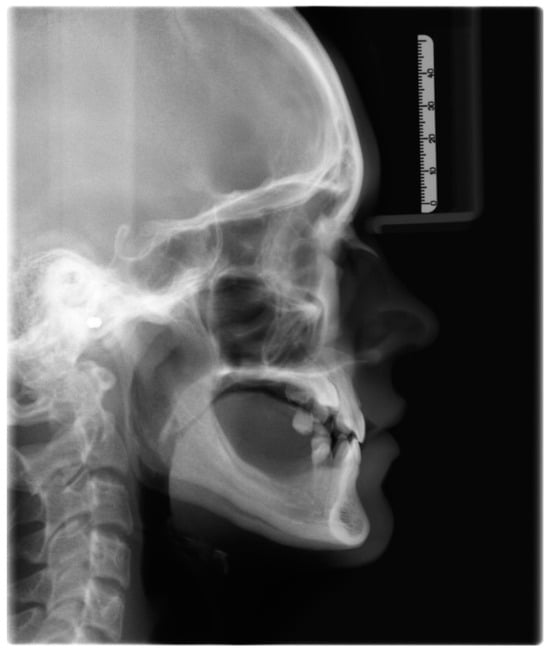

| Measurement | Norm | Deviation | Value |

|---|---|---|---|

| SNA | 82.0° | ± 3.0 | 82.9° |

| SNB | 80.0° | ± 3.0 | 83.6° |

| ANB | 2.0° | ± 2.0 | −0.7° |

| SNPg | 81.0° | ± 3.0 | 86.0° |

| GntgoAR | 122.0° | ± 7.0 | 121.8° |

| NL-NSL | 8.0° | ± 4.0 | 3.1° |

| ML-NSL | 28.0° | ± 5.0 | 26.2° |

| ML-NL | 20.0° | ± 7.0 | 23.1° |

| 1+:NA | 21.0° | ± 4.0 | 17.2° |

| 1+:NA (mm) | 3.7 mm | ± 2.0 | 3.2 mm |

| 1+:NL | 110° | ± 6.0 | 104° |

| 1−:NB | 24.0° | ± 4.0 | 10.5° |

| 1−:NB (mm) | 3.8 mm | ± 2.0 | 0.4 mm |

| 1−:ML | 94° | ± 7.0 | 79.2° |

| 1−:APg | 1.0 mm | ± 2.0 | −1.4 mm |

| 1+:1− | 133.0° | ± 8.0 | 153.5° |

| UL—“E” plane | −4.7 mm | ± 2.0 | −4.35 mm |

| LL—“E” plane | −2.0 mm | ± 2.0 | −4.45 mm |

| Measurement | Pretreatment | Posttreatment | Difference |

| SNA | 82.9° | 83.4° | 0.5° |

| SNB | 83.6° | 85.0° | 1.4° |

| ANB | −0.7° | −1.6° | −0.9° |

| SNPg | 86.0° | 87.7° | 1.7° |

| GntgoAR | 121.8° | 116.3° | −5.5° |

| NL-NSL | 3.1° | 4.8° | 1.7° |

| ML-NSL | 26.2° | 22.0° | −4.2° |

| ML-NL | 23.1° | 17.2° | −5.9° |

| 1+:NA | 17.2° | 32.1° | 14.9° |

| 1+:NA (mm) | 3.2 mm | 5.4 mm | 2.2 mm |

| 1+:NL | 104° | 117.2° | 13.2° |

| 1−:NB | 10.5° | 13.7° | 3.2° |

| 1−:NB (mm) | 0.4 mm | −0.1 mm | −0.5 mm |

| 1−:ML | 79.2° | 85.7° | 6.5° |

| 1−:APg | −1.4 mm | −1.2 mm | 0.2 mm |

| 1+:1− | 153.5° | 135.8° | −17.7° |

| UL—“E” plane | −4.35 mm | −5.02 mm | −0.67 mm |

| LL—“E” plane | −4.45 mm | −3.62 mm | 0.83 mm |